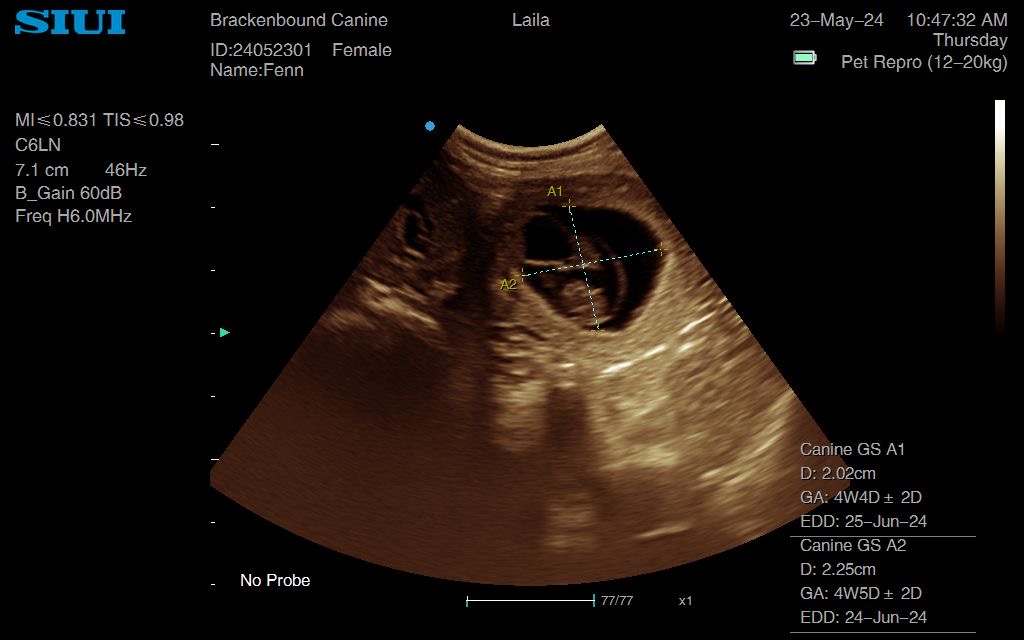

I used both GSD and CRL measurements on 2 different embryos to calculate an estimated due date for this working Labrador pregnancy

Gestational sac measurements for working Labrador Fenn. This was a sad case actually. All seemed to be going well but Fenn was part of a fairly large house move and